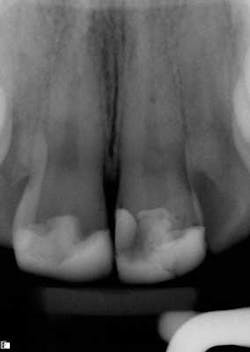

These are my least favorite teeth to treat. Most are heavily restored and the mesial-distal dimension is very small, resulting in no margin for error when locating the pulp chamber. Additionally, there can be significant inclination between the crown and root, and many will have two canals or branching at some level of the canal. (12,15) This lingual inclination of the root results in difficulty obtaining straight-line access into the buccal canal and makes locating the lingual canal almost impossible in some cases, especially if the lingual shelf of dentin is prominent. (Figure 2) Straight-line access into some lingual canals would need to be established through the mid-facial, and this is not a reasonable option for teeth restored with full-coverage crowns. (16)

have two canals. The second canal is lingual

to the main canal, and it is not uncommon for

the two canals to join at the apex. Tooth

No. 24 has a necrotic pulp and based on

the anatomy of teeth Nos. 23 and 26, a

second canal in tooth No. 24 should be expected.